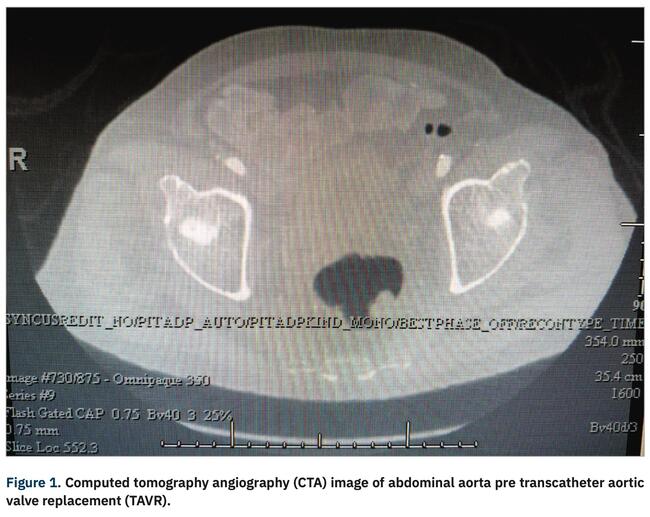

Prior to the TAVR procedure, a computed tomography angiography (CTA) is utilized in part to help identify vascular access risks. The luminal diameter of the access vessels, presence of any dissections, height of bifurcation vessels, and calcium burden are essential to evaluate and ensure a successful percutaneous approach. For the 26 mm Sapien 3 Ultra valve (Edwards Lifesciences), the product literature states the requirement of a minimum diameter of 5.5 mm for the 14 French delivery system.